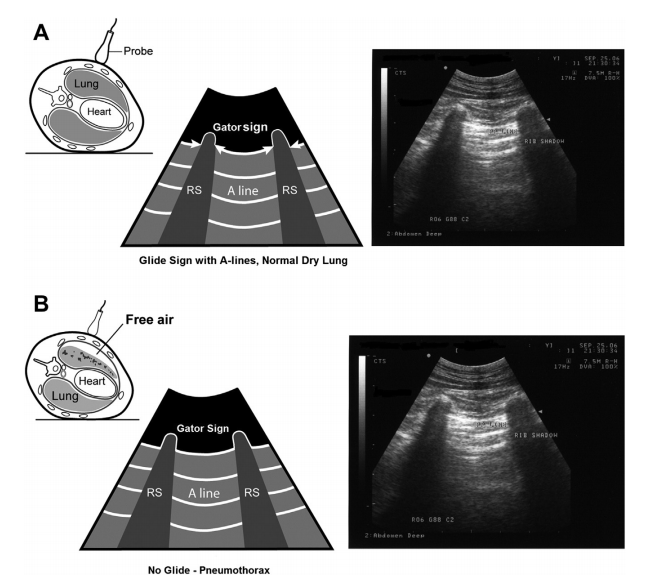

The pulmonary-pleural interface (PP-line) is not to be confused by the distally positioned equidistant reverberation artifacts A-lines (air reverberation artifact) that parallel and extend from the PP-line.

A-lines are

air artefact, reverberation

sideways